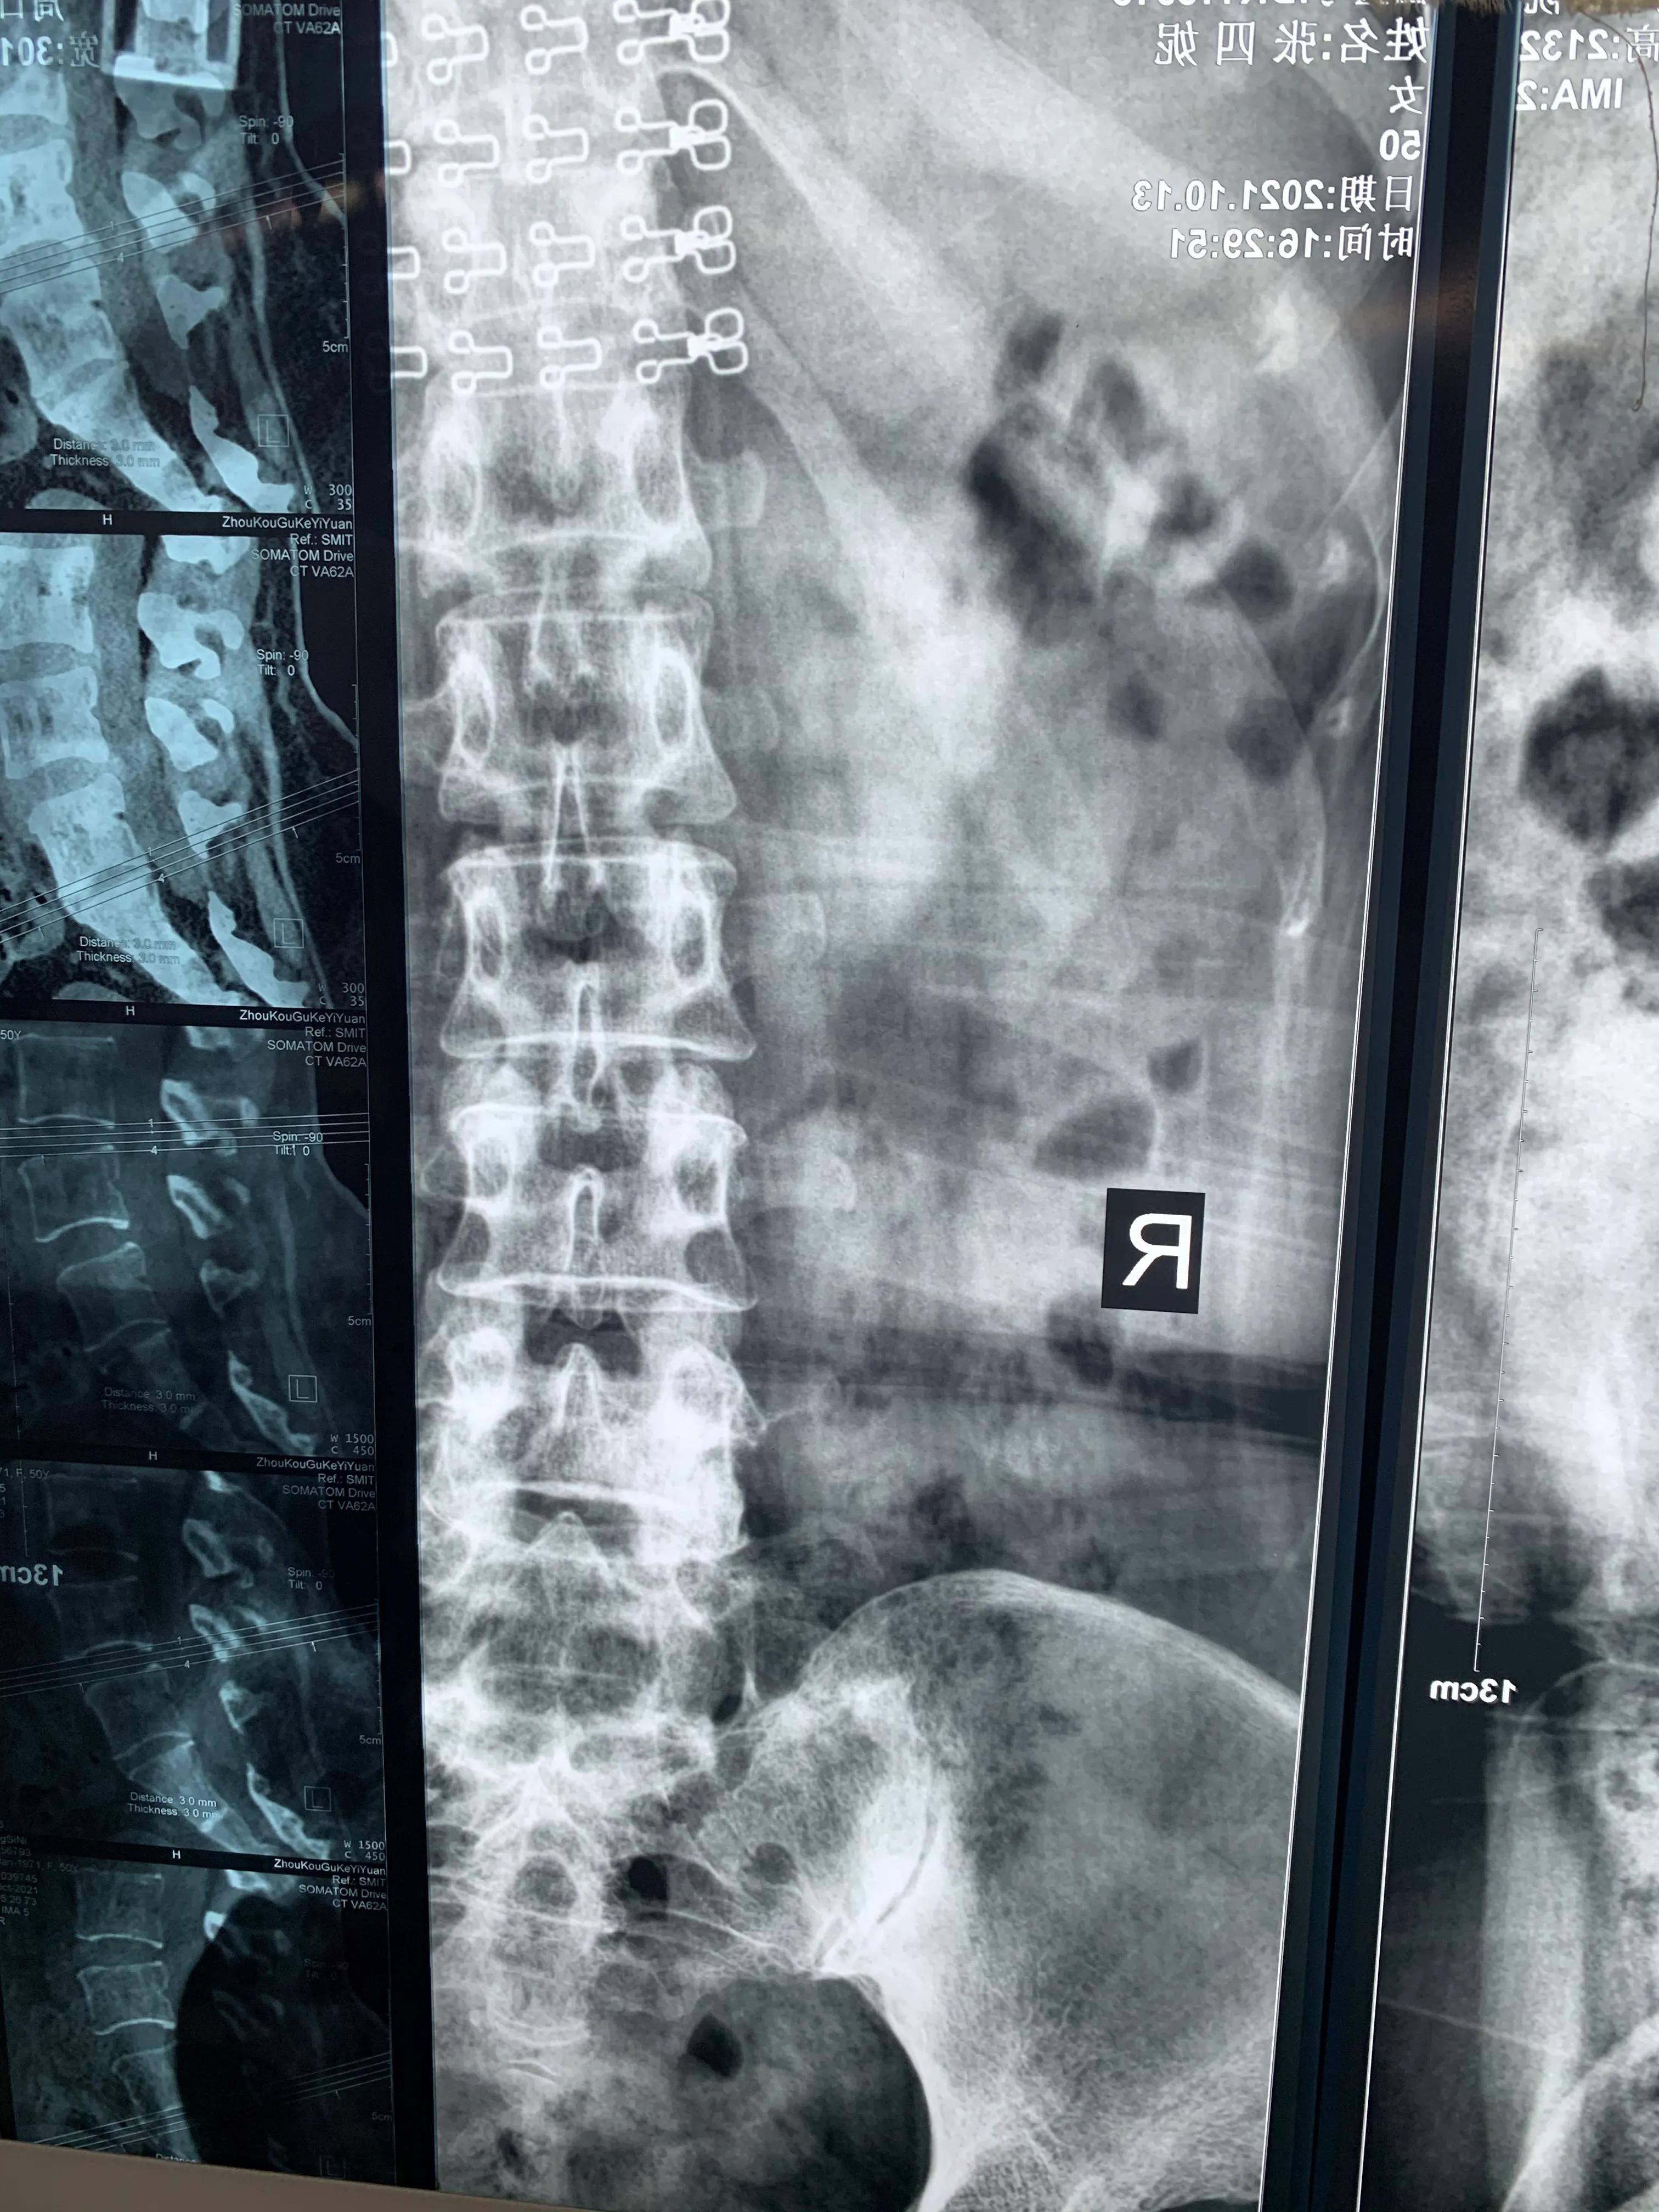

术前X线片